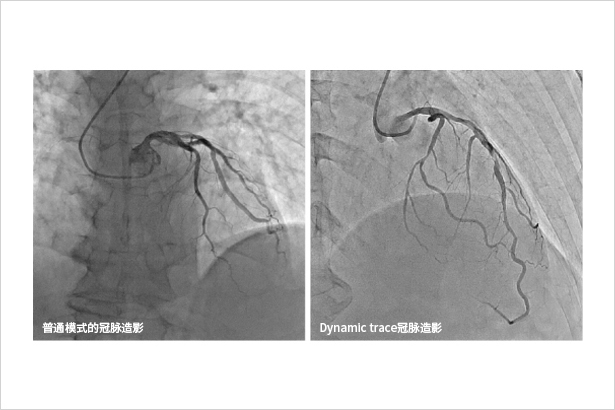

Dynamic trace主要用于下肢造影、心臟介入等影像密度差異較大的介入手術